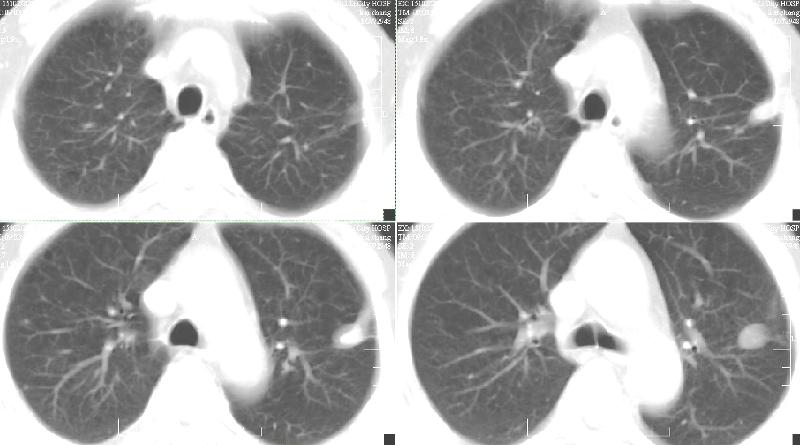

标题: CT19134:M,58岁。咳嗽痰多一月,不发热。 [打印本页]

标题: CT19134:M,58岁。咳嗽痰多一月,不发热。

ct:慢性支气管炎,(轻度泡性气肿),并左上叶尖后段结核球(可能大)。2、左下叶背段小片感染(考虑结核)